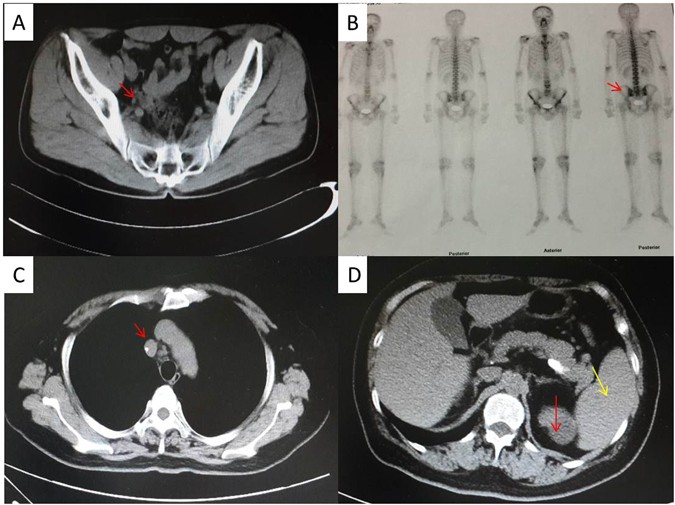

Case 1: a 40-years old man visited the outpatient clinic presenting a two-week history of a painless mass in his left inguinal. The patient had foot nail removal for paronychia caused by trauma five years ago. No skin moles and tumor was found at lower limbs. The patient had no family cancer history and was in good health before. Ultrasound showed one low echo node in the right neck, the size being 0.9 × 0.2 cm; some low echo nodes in the left neck, the biggest size being 0.5 × 0.3 cm; some low echo nodes in the right inguinal, the biggest size being 0.8 × 0.3 cm; some low echo nodes in the left inguinal, the biggest size being 1.3 × 1.0 cm. All of the nodes had clearly border and regular contour. Pelvic CT (Fig. 8A) showed the lymph nodes aside the left external iliac blood vessels enlarged and the biggest one was 1.8 × 1.4 cm, but there was no enlarged lymph node in the right external iliac blood vessels and retroperitoneal. There was no abnormality in the liver and spleen. PETCT (Fig. 8B) displayed a high bone salt metabolism in right coracoid and left sacroiliac joint, indicating a benign lesion. Blood and bone marrow aspiration were normal.

Pelvic CT scanning in case 1 displayed the lymph nodes aside the left external iliac blood vessels enlarged, with the biggest size of 1.8 × 1.4 cm (A). PETCT in case 1 showed a high bone salt metabolism in right coracoid and left sacroiliac joint (B). Chest CT scanning in case 2 displayed multiple lymph nodes enlarged in right hilar and mediastinal (C). Abdomen CT scanning in case 2 displayed a clear borderline mass in the right kidney (red arrow) and a slightly larger spleen (yellow arrow) (D).

Case 2: a 62-years old woman presented cough and hard breath for 3 months. Superficial lymph nodes were not touched and blood test was normal. Chest CT (Fig. 8C) scan showed: multiple lymph nodes enlarged in right hilar and mediastinal, multiple nodules with calcification in the upper lobe of right lung and some patchy enhancement spot in the middle of the upper lobe, left lower lobe and secondary adjacent bronchiectasis. Abdomen CT (Fig. 8D) scan showed a clear borderline mass in the right kidney, with the size of 4.4 × 4.1 × 5.8 cm, and a slightly larger spleen. Mediastinal lymph node was biopsied and pathological diagnosis was tending to be metastasis of poorly differentiated carcinoma with a large number of necrosis. The patient had two cycles chemotherapy of paclitaxel and nedaplatin but the disease progressed. The patient had mediastinal lymph node biopsy again.